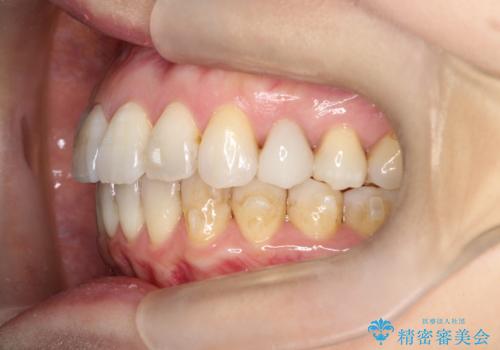

【インビザライン 】前歯を下げたい

- 前歯の凸凹と、前突を主訴に来院されました。

インビザライン にて治療を行なっております。

治療期間中はゴムかけを行なってもらうことで、前歯を下げることができました。